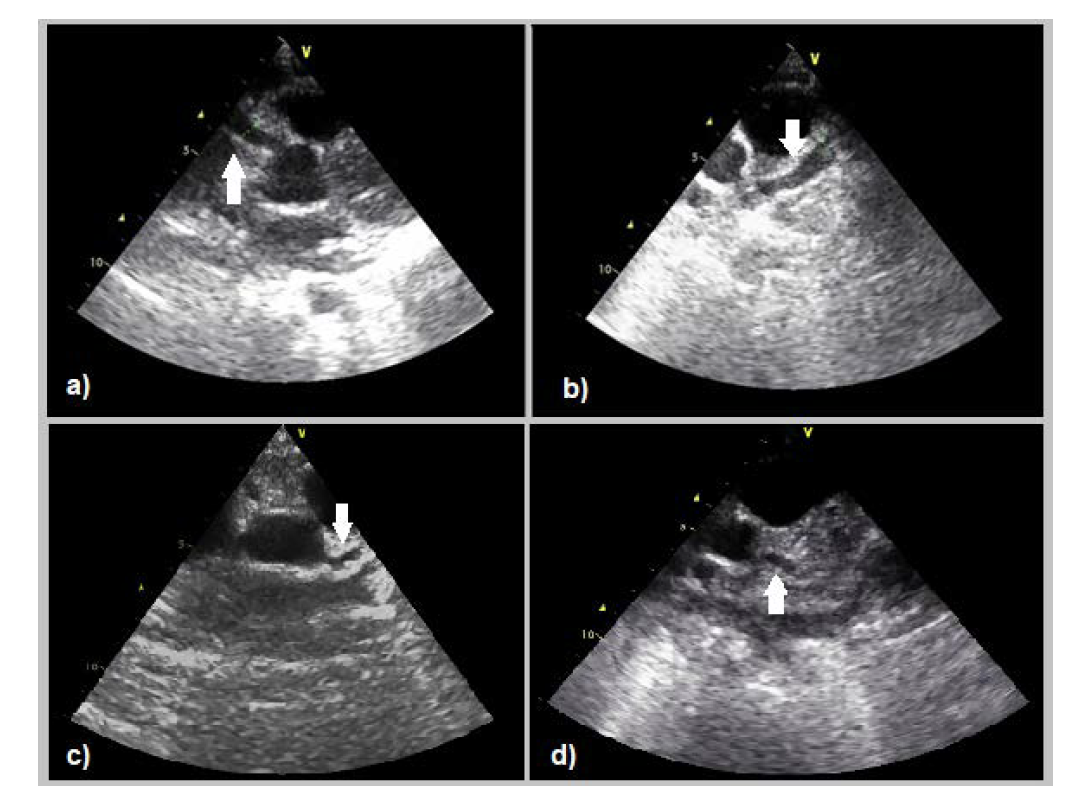

Case 1

A five-year-old boy with refractory Kawasaki disease developed bilateral proximal coronary artery aneurysms within the first 10 days of the disease, the largest in the right coronary artery, with a diameter of 6.0 mm (Z-score of +9.16). He required a further immunoglobulin dose and, eventually corticosteroids before the inflammatory process settled. The aneurysms persisted on echocardiogram and a year later, a coronary artery angiogram (Figure 1) revealed a significant, right coronary artery saccular aneurysm with moderate dilatation of the anterior descending artery.

To date, the lesions persist with a right coronary artery saccular aneurysm (Z-score of +7.15) on a transthoracic echocardiogram, consistent with a 4.1 type of coronary abnormality according to the American Heart Association risk classification system.1 The patient is now 11 years old, is asymptomatic, and on anti-platelet therapy. A treadmill stress test and adenosine stress cardiac magnetic resonance have shown no signs suggestive of cardiac ischemia.